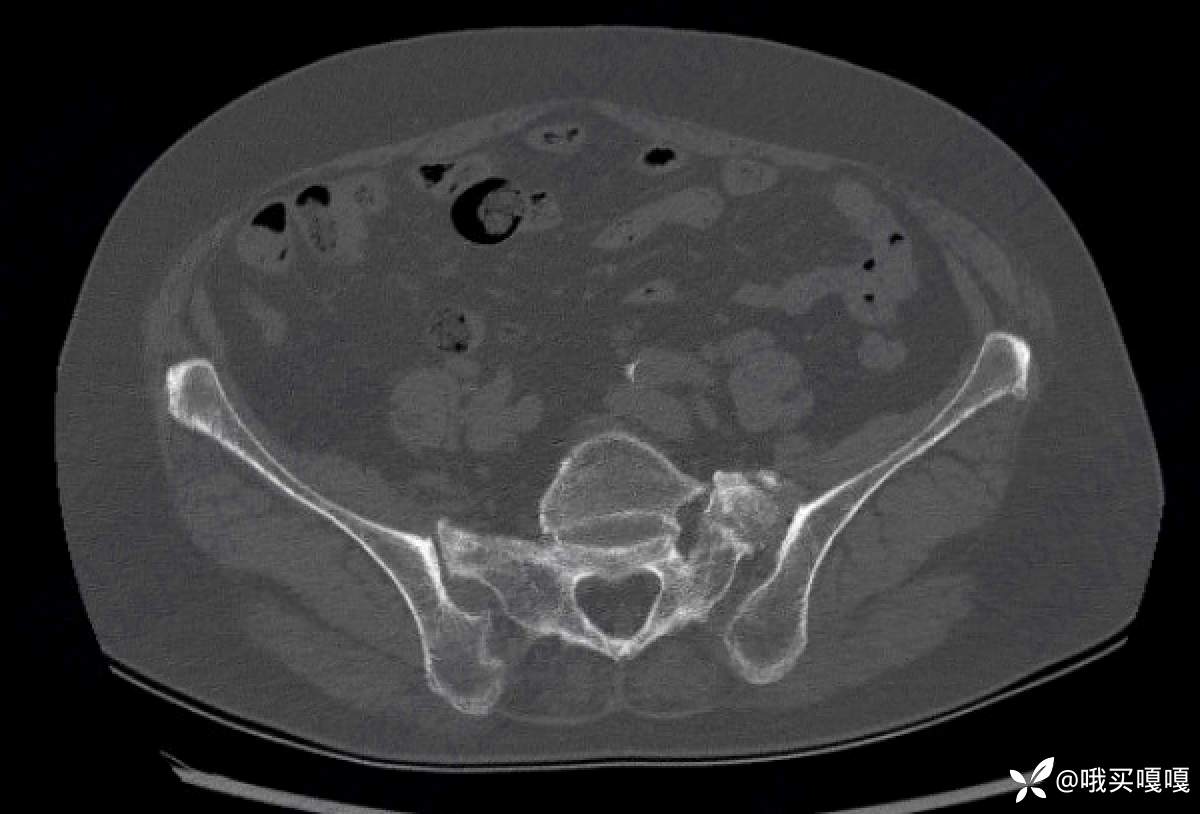

请问各位,这个骶髂关节的CT,看起来像脊柱关节炎引起骶髂关节炎的影像学改变吗?